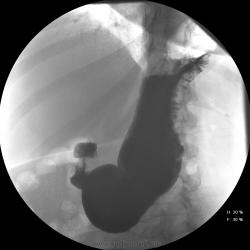

Женищина 49 лет, повышенного питания, обратилась с жалобами на потерю аппетита, жжение после чуть острой пищи, отрыжку с неприятным запахом, иногда темный стул, несколько похудела. Данные жалобы с сентебря-октября. Никуда не обращалась, коррегировала питанием. В последнее время стало хуже, обратилась...

Привратник удлиннен и ригиден, такое бывает при раке. Рек. ЭГДС.

Вы правы. я несколько недорасказал. женщина пришла уже с фгдс - инфильтративно-язвенный процесс в выходном отеде желудка у привратника по малой кривизне с переходом на переднюю стенку. так что прицельно смотрел этот отдел. перистальтка была ослаблена, краевой дефект в препилорической зоне по малой кривизне, передней стенке, кажущееся удлинение привратника, нависание основания луковицы - вообщем как в книжке. эвакуация было не изменена. написал рак выходного отдела желудка. вчера пришла гистология - высокодиф-я аденокарцинома. вот такая история.

Пока, касаясь только луковицы, но не препилорического отдела. "Ниши" в луковице есть, и они нуждаются в объяснении.

Конечно, в пилорическом канале уже растет, и "это" растет, уже и препилорической части и в луковице 12-ти перстной кишки.